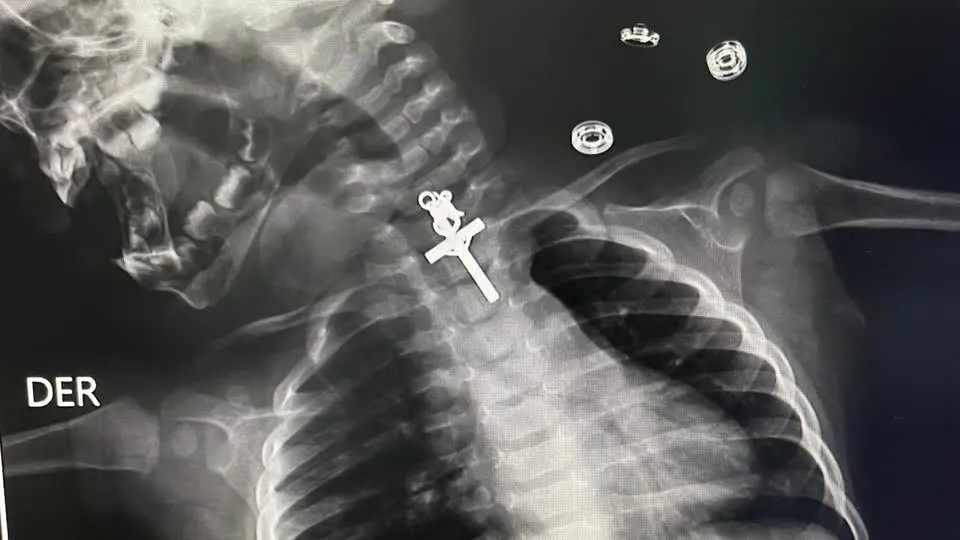

Crucifixo é detectado por meio de Raio-X na garganta de bebê

Uma equipe médica realizou uma endoscopia para remover o objeto estranho, um crucifixo, da região superior do esôfago.

O procedimento, realizado no último sábado (11), foi descrito como desafiador pelo médico responsável, Luis Esteves Cabanillas.

“O procedimento foi muito complicado porque era um crucifixo e estava alojado no terço superior do esôfago. Mesmo quando tentamos retirá-lo inicialmente, não conseguimos, estava preso, então tentamos várias vezes até que conseguimos retirar o corpo estranho”, explicou o médico.